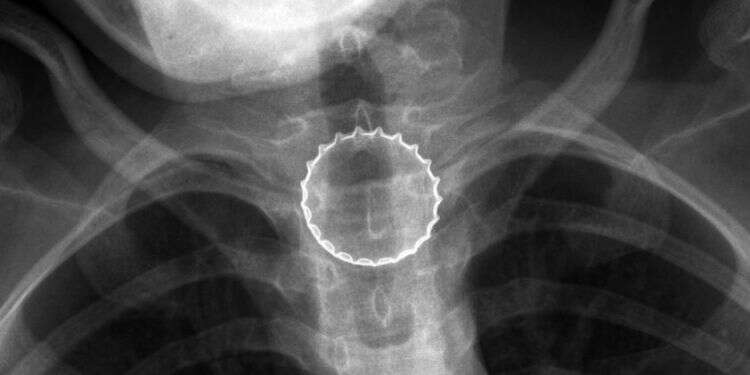

במיון ילדים עברה הנערה בירור מקיף ויסודי ע"י צוות בראשות ד"ר עלי ח'טיב, מומחה ברפואת ילדים, ובין השאר בוצע לה צילום רנטגן, בו התגלה גוף זר בוושט. הנערה הוכנסה לחדר ניתוח, שם – באמצעות ציוד אנדוסקופי ייעודי – הוצא מצינור הוושט פקק של בירה קורונה ע"י צוות ממחלקת אף אוזן גרון וניתוחי ראש-צוואר, בניהולו של ד"ר אייל סלע. הנערה אושפזה להשגחה למשך יממה ושוחררה במצב טוב.